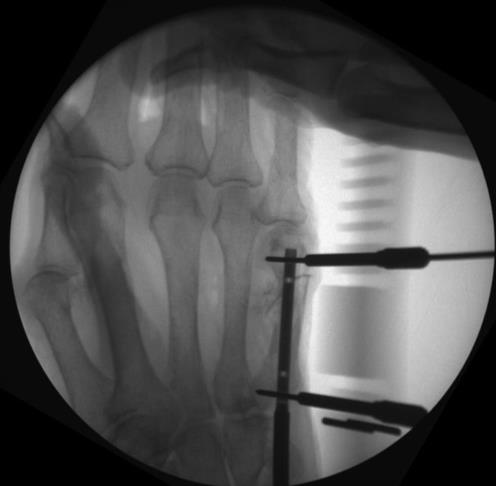

• step 6

• advance the 2.0mm stop drill through the selected proximal slot, drilling through the near cortex until the mechanical stop reaches the drill guide

• measure screw length with the 1.4mm drill, stopping before the far cortex

• insert the selected 1.8mm locking compression screw unicortically

• step 7

• confirm final reduction and implant position using fluoroscopy

• step 8

• repeat the drilling, sizing, screw insertion, and fluoroscopic confirmation steps for the distal screw, taking note of the chosen hand nail length and the drill guide etched sizes